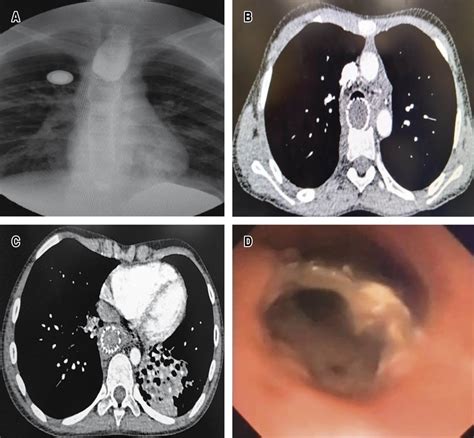

The placement of a stent in esophagus is generally performed by a gastroenterologist or a specialized thoracic surgeon. The procedure is typically minimally invasive and is conducted under sedation or light anesthesia.

1. Endoscopic Guidance: The doctor inserts an endoscope—a thin, flexible tube with a camera—down the throat to visualize the narrowed area.

2. Measurement: Using X-ray imaging (fluoroscopy) or direct visual inspection, the physician measures the exact length and width of the obstruction to select the appropriately sized stent.

3. Deployment: The stent is loaded onto a delivery system and guided into the esophagus. Once positioned correctly across the blockage, the stent is deployed, where it expands against the esophageal walls.

4. Verification: The physician confirms the stent is properly seated before removing the delivery catheter.